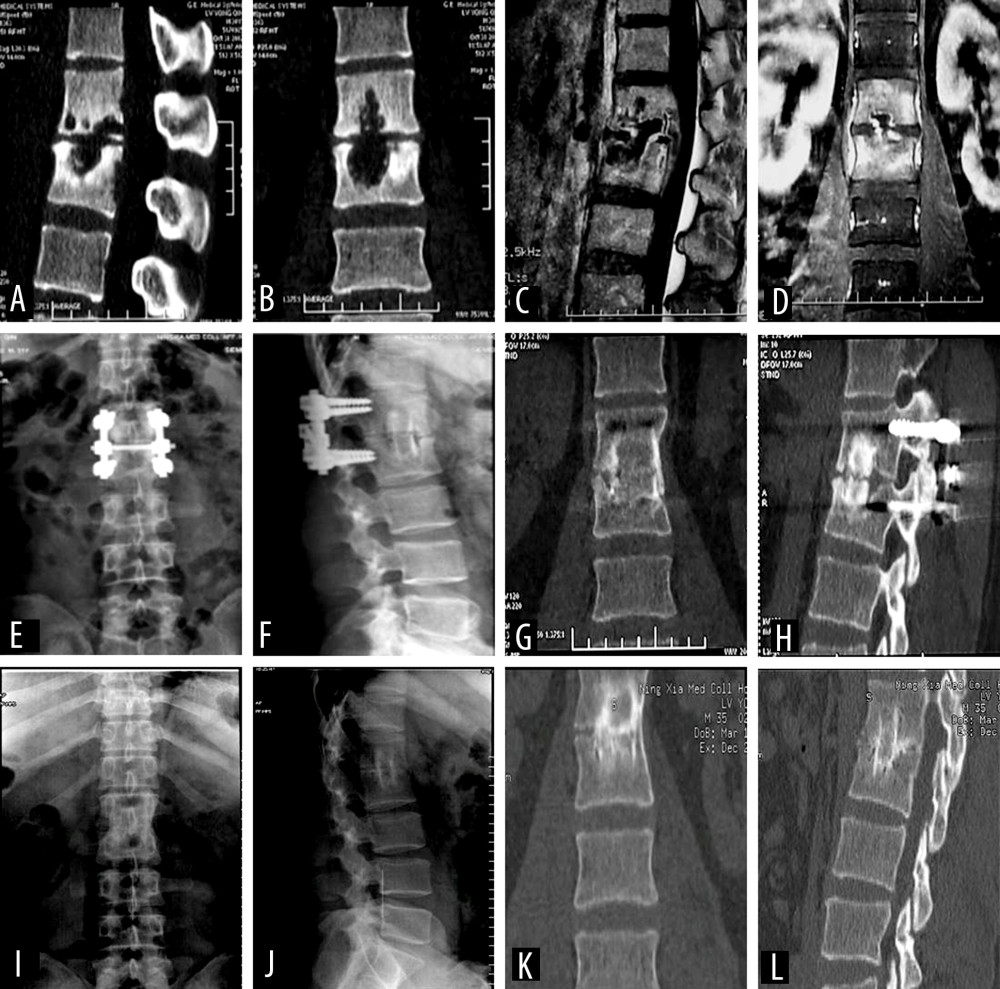

Figure 3. A 30-year-old male patient diagnosed with L1–2 vertebral tuberculosis was treated with posterior affected-vertebrae fixation, anterior subdiaphragmatic extraperitoneal approach for thorough lesion removal, and autologous iliac bone graft fusion. (A, B) Preoperative computed tomography (CT) showed obvious bone destruction. (C, D) Enhanced magnetic resonance imaging before surgery showed vertebral signal changes, vertebral bone destruction, and paravertebral abscess. (E–H) X-ray and CT at 6 months after surgery showed pedicle screw fixation and good bone graft fusion. (I–L) X-ray and CT 5 years after surgery showed that the pedicle screw had been completely removed, the lesion had completely cured, and the bone graft had completely fused. Tables